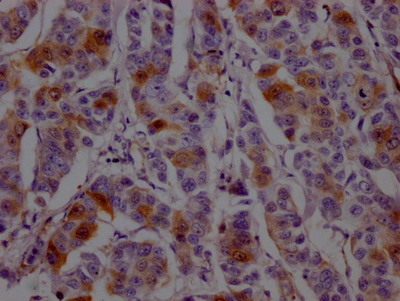

IHC image of CSB-RA264582A0HU diluted at 1:100 and staining in paraffin-embedded human breast cancer performed on a Leica BondTM system. After dewaxing and hydration, antigen retrieval was mediated by high pressure in a citrate buffer (pH 6.0). Section was blocked with 10% normal goat serum 30min at RT. Then primary antibody (1% BSA) was incubated at 4℃ overnight. The primary is detected by a Goat anti-rabbit IgG polymer labeled by HRP and visualized using 0.05% DAB.